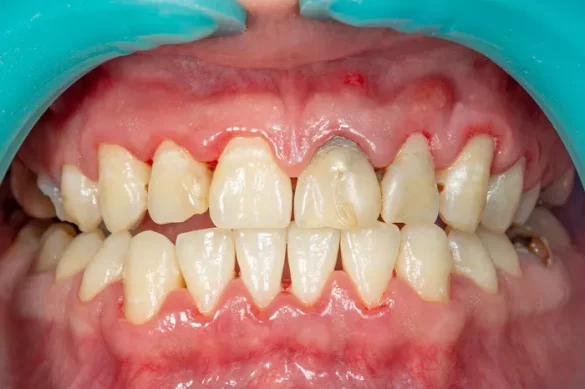

The main symptoms of gingivitis include red, swollen gums. The gums may also bleed easily, especially during brushing or flossing. There may be a bad taste in the mouth or a persistent bad breath. For instance, a patient with gingivitis might notice that their gums bleed when they brush their teeth in the morning. The gums may have a shiny appearance and be tender to the touch. However, at this stage, the disease has not yet affected the bone and ligament that support the teeth.

Symptoms of periodontitis include deepening of the gum pockets. Normally, the space between the gum and the tooth is very small, but in periodontitis, this space can increase as the gum tissue pulls away from the tooth. There may be tooth mobility, where the teeth feel loose. Bad breath and a bad taste in the mouth may become more pronounced. For instance, a patient may notice that their front teeth are starting to feel wobbly, and they have a persistent unpleasant smell coming from their mouth. There may also be gum recession, where the gums pull back and expose more of the tooth root.